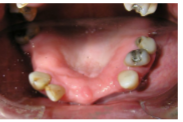

4) Restorations of upper and lower teeth

6) Study models/dental casts